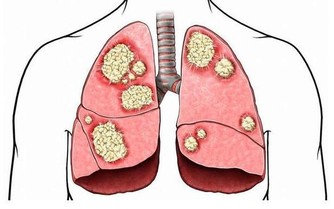

吸煙的壞處不用多提,除了肺癌、糖尿病等,它還會加劇慢性頸椎痛。

吸煙會減少背部和頸部骨頭中的水分,從而加速這些部位的退化,嚴重可導致椎間盤突出,影響脊椎正常功能。另外,吸煙還會使血管硬化,使得輸送至脊椎和骨頭的氧氣量減少。